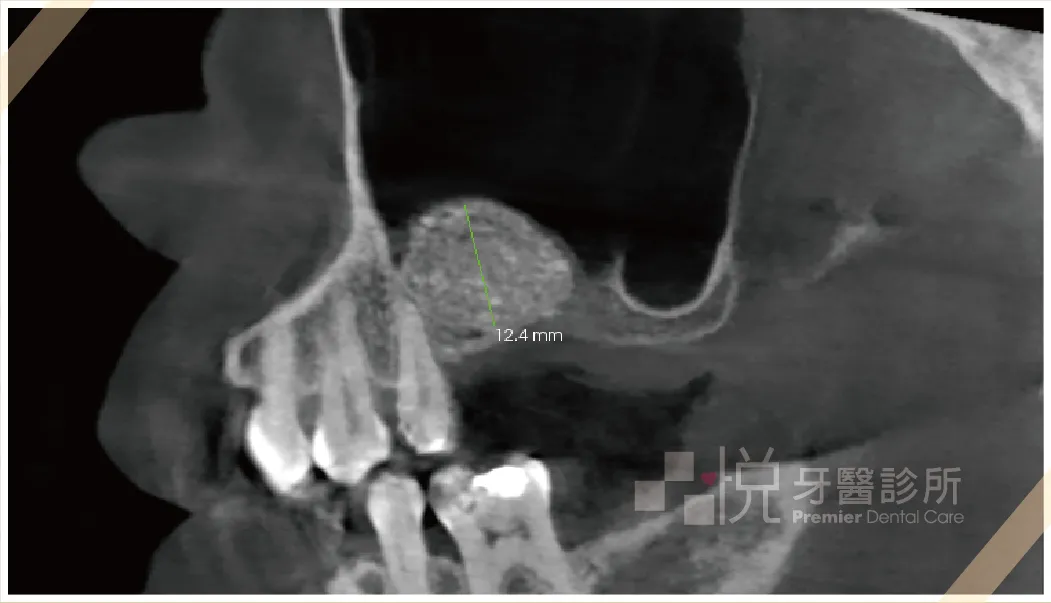

➍ 側方開窗法術後x光確認術後結果,有顆粒感的白色部分為放入置骨粉,原本 1mm 提升至12mm。

➎ 術後 X 光片顯示,鼻竇膜被安全剝離,並成功填塞骨粉,等待骨頭成長後再植入植體。